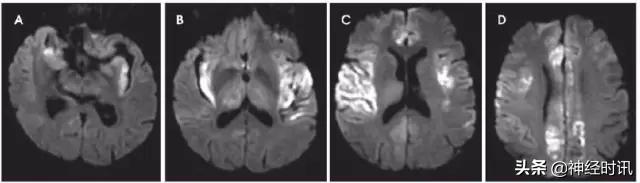

短暂性全面性遗忘(TGA)

TGA是急性发生的一过性顺行性记忆丢失。发病机制不明,但缺血、癫痫和偏头痛是可能的机制。典型表现为海马斑点状弥散受限(图5)。一项报告显示,从发病到影像学检查的时间由8小时增加到48小时,DWI阳性的发现率由5%增加到85%。

图5 一例51岁女性,表现为意识不清,言语含糊,近事遗忘。发病后4天DWI显示双侧海马点状弥散受限(A&B:DWI;C&D:ADC)。随访MRI显示病灶完全缓解(图像未提供)。